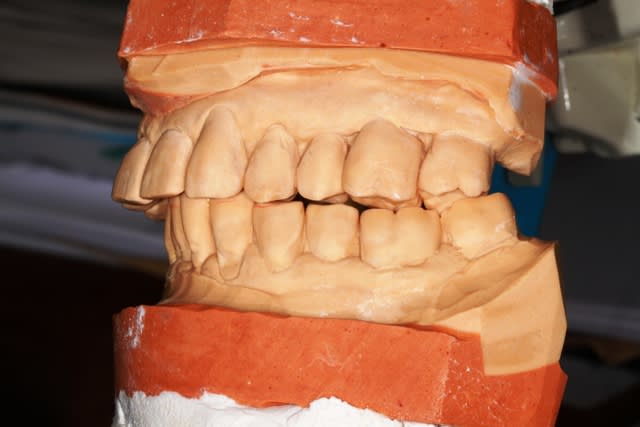

revue la patiente ce jour...avec un joli scan...rien de réjouissant.

Néanmoins, le plan de travail se met en place, et aujourd'hui, détartrage (irrigation à la betadine) constat que le terrain est miné, mais je vais quand même jouer la conservation.

Empreintes pour préparer un Waxup

les conseils sont les bienvenus, bien sur

Pourquoi conserver? parce que je crois que c'est la bonne voie

Ensuite si la situation se dégrade, il sera toujours temps de pratiquer les avulsions